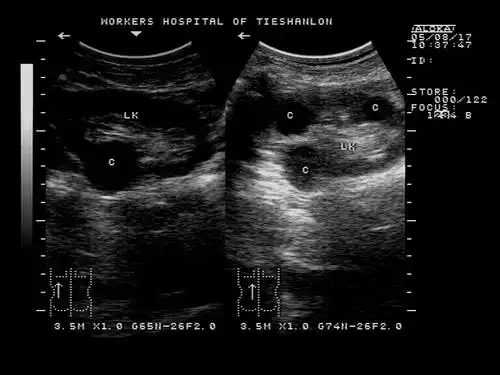

【共享】自己收藏的超声图片,和大家共享哦